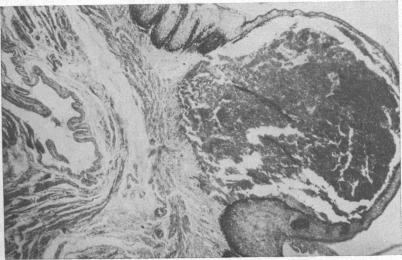

Endoesophageal sclero-therapy of bleeding esophageal varices.

J Cardiovasc Surg (Torino). 1971 Mar-Apr;12(2):146.